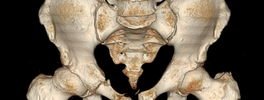

3D CT Pelvis